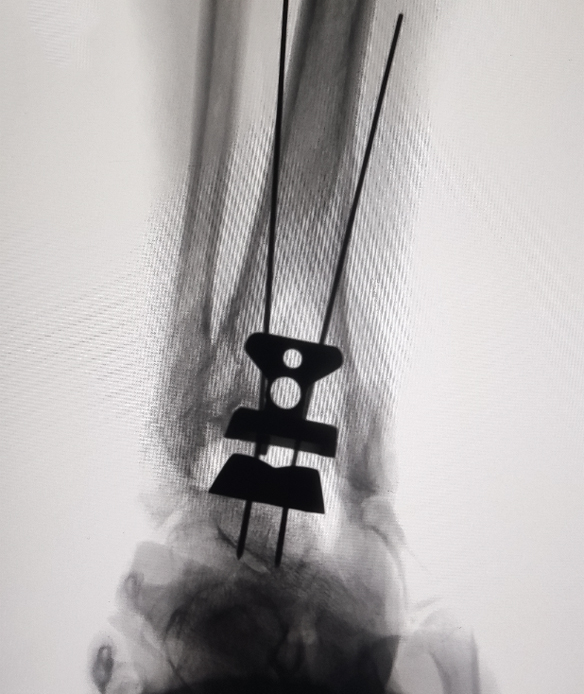

在为贾女士进行综合评估后,手足外科吕振刚副主任医师团队决定为她实施右踝关节置换术。手术由吕振刚主刀,桂琦副主任医师、赵英伦主治医师协作完成。术中,术者精准截骨,最大程度恢复关节力线;结合术中影像,确保假体定位精准;选择合适假体系统,增强了术后的稳定性与耐久性。

手术顺利完成,贾女士术中生命体征平稳,无并发症,踝关节疼痛症状明显缓解,并于近日顺利出院。